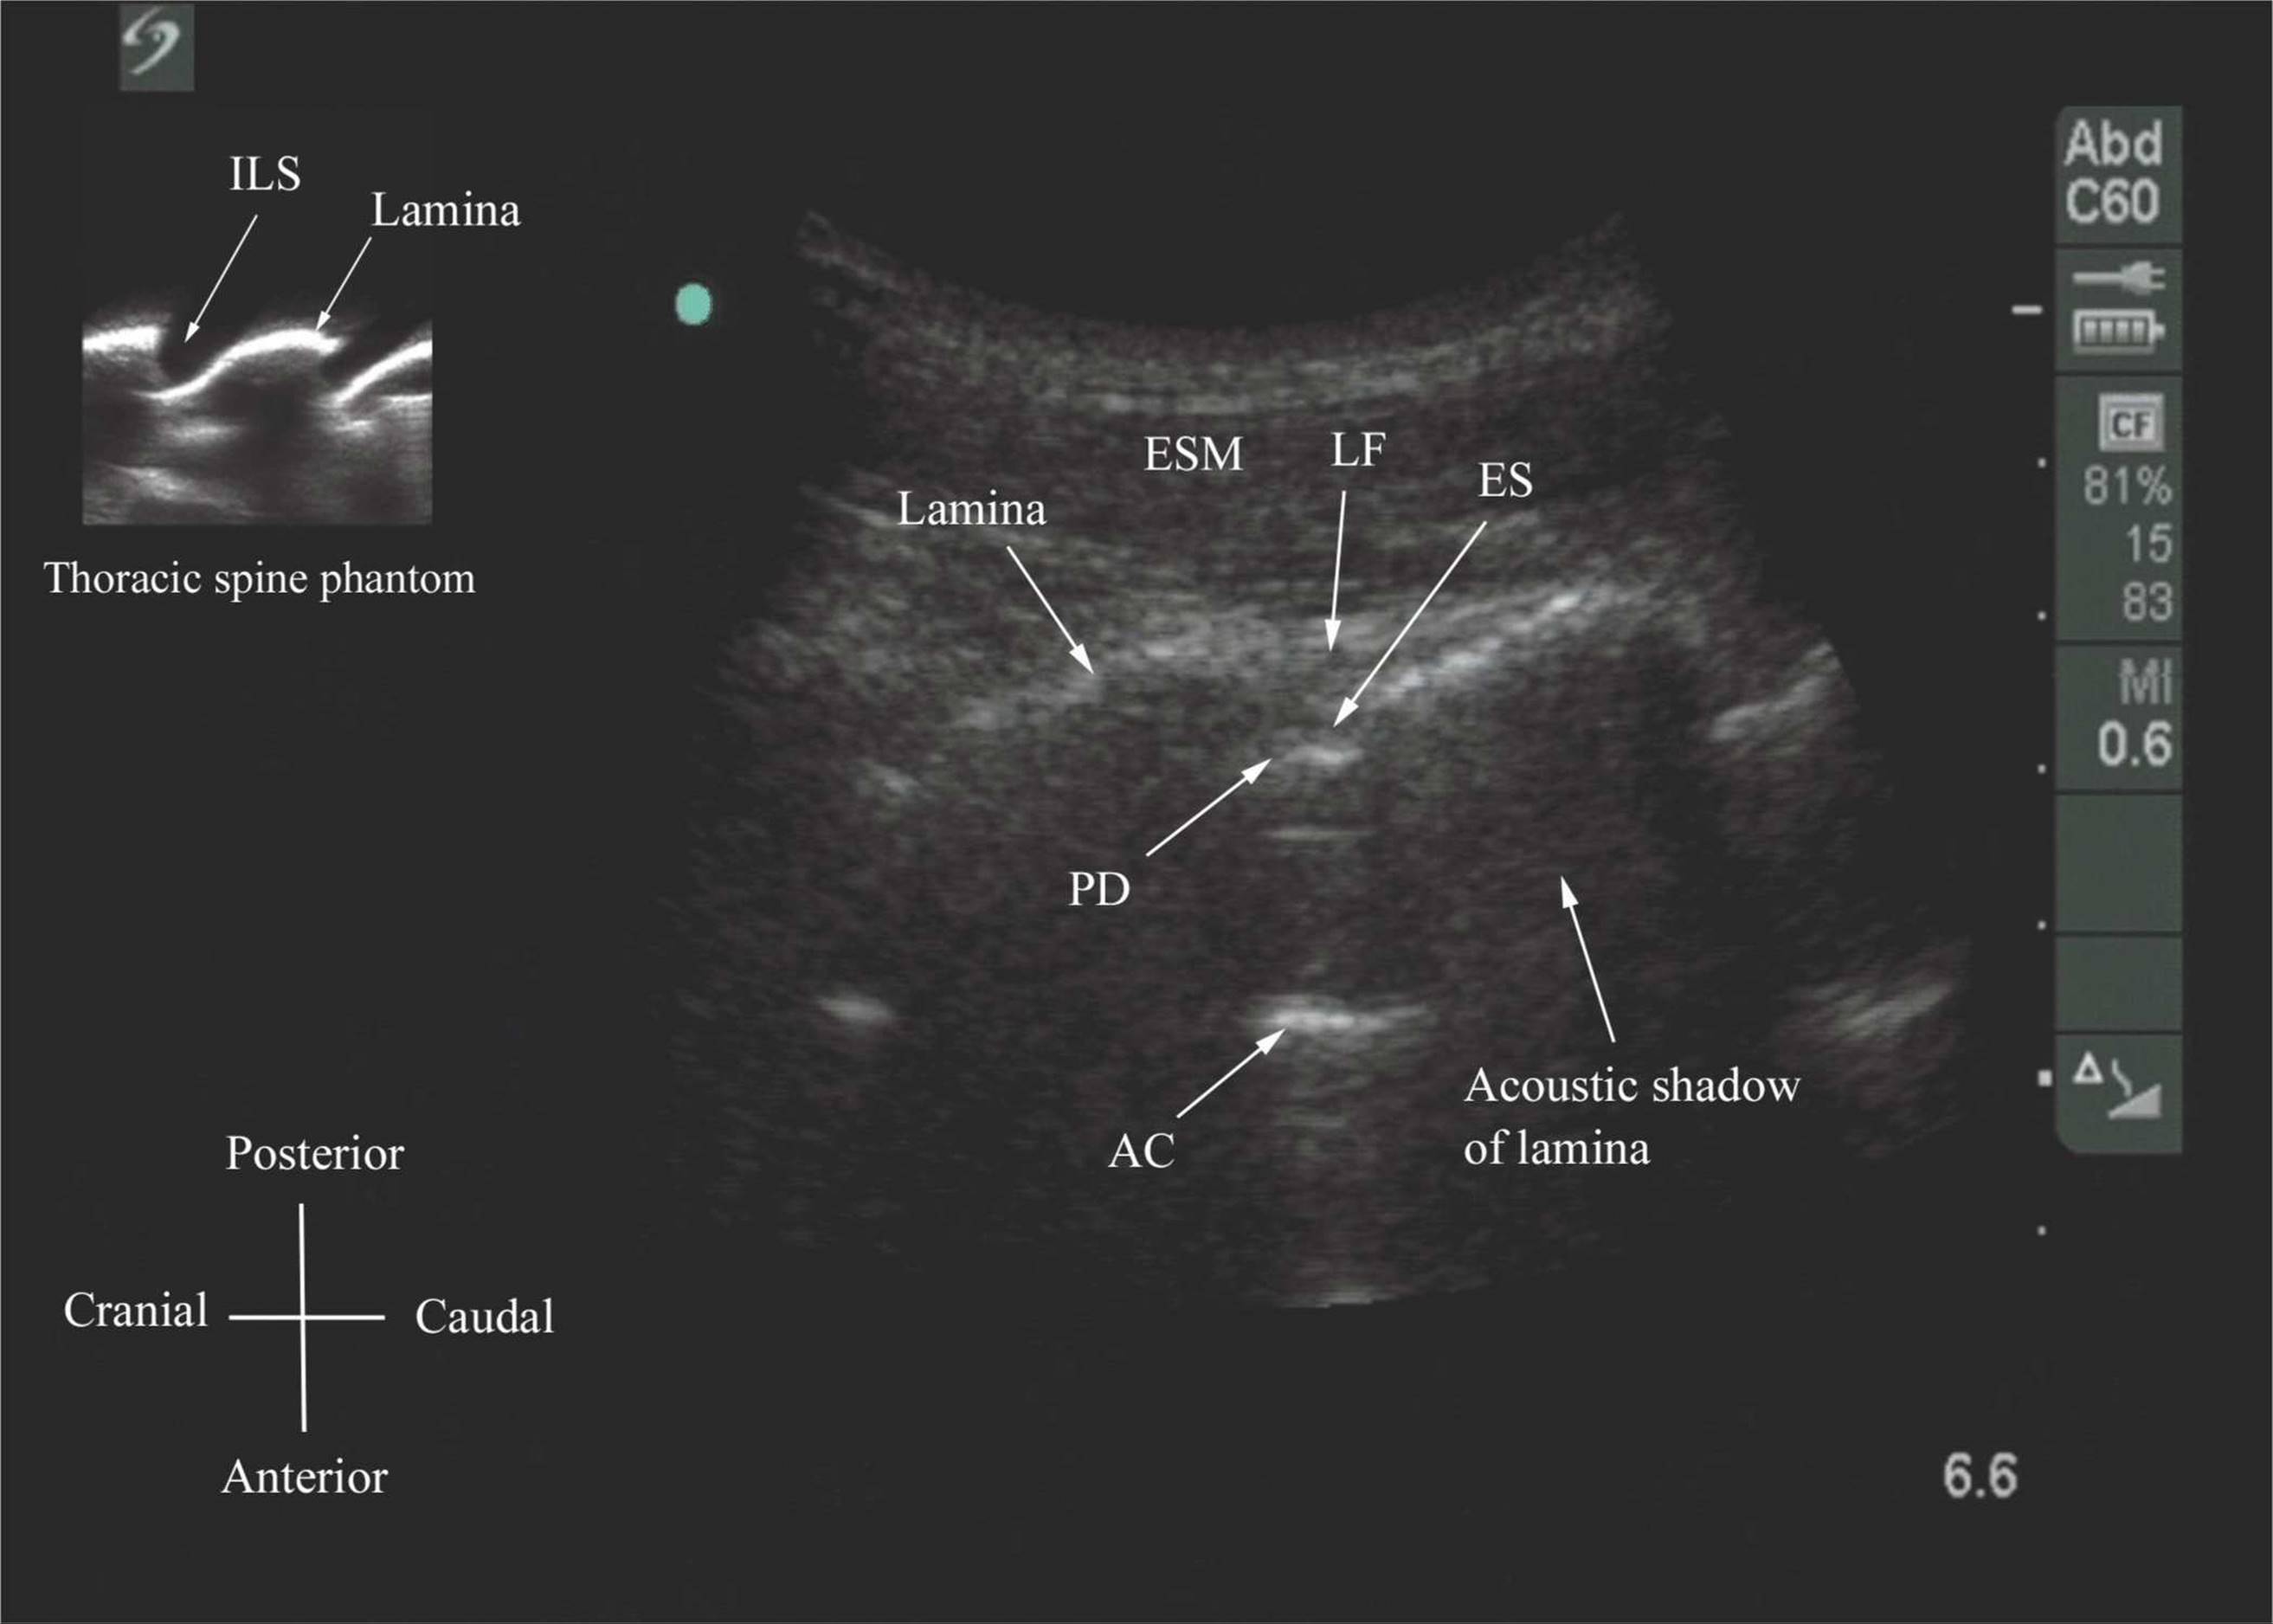

Ultrasound guide

Ultrasound guide 108 фотографий